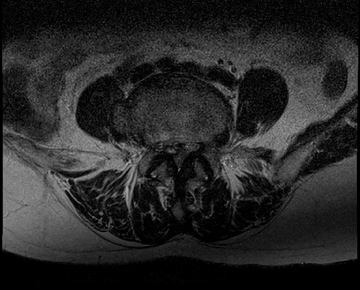

요추 협착증 수술 전·후

2020.08.30

2022.09.06

ㆍ환자 동의를 받은 자료이며, 이미지 사진은 실물과 다를 수 있습니다.

ㆍ모든 자료는 새움병원 자료입니다.